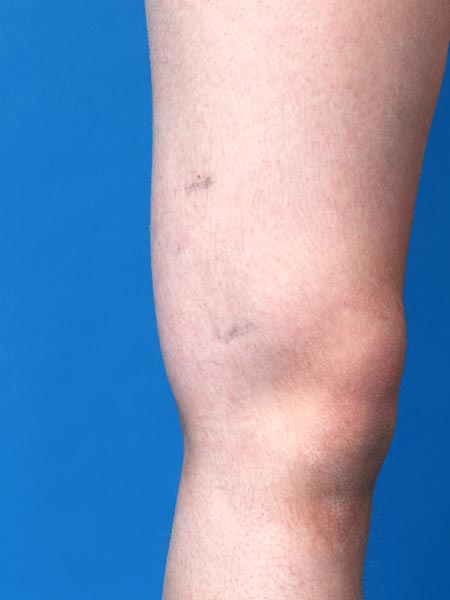

12-year-old female patient with circumscribed, relatively soft palpable swelling on the lateral distal thigh. Dysplastic veins are visible on the skin in 2 places. In the area of the swelling, recurrent induration and circumscribed pain due to thrombophlebitis in the venous malformation.